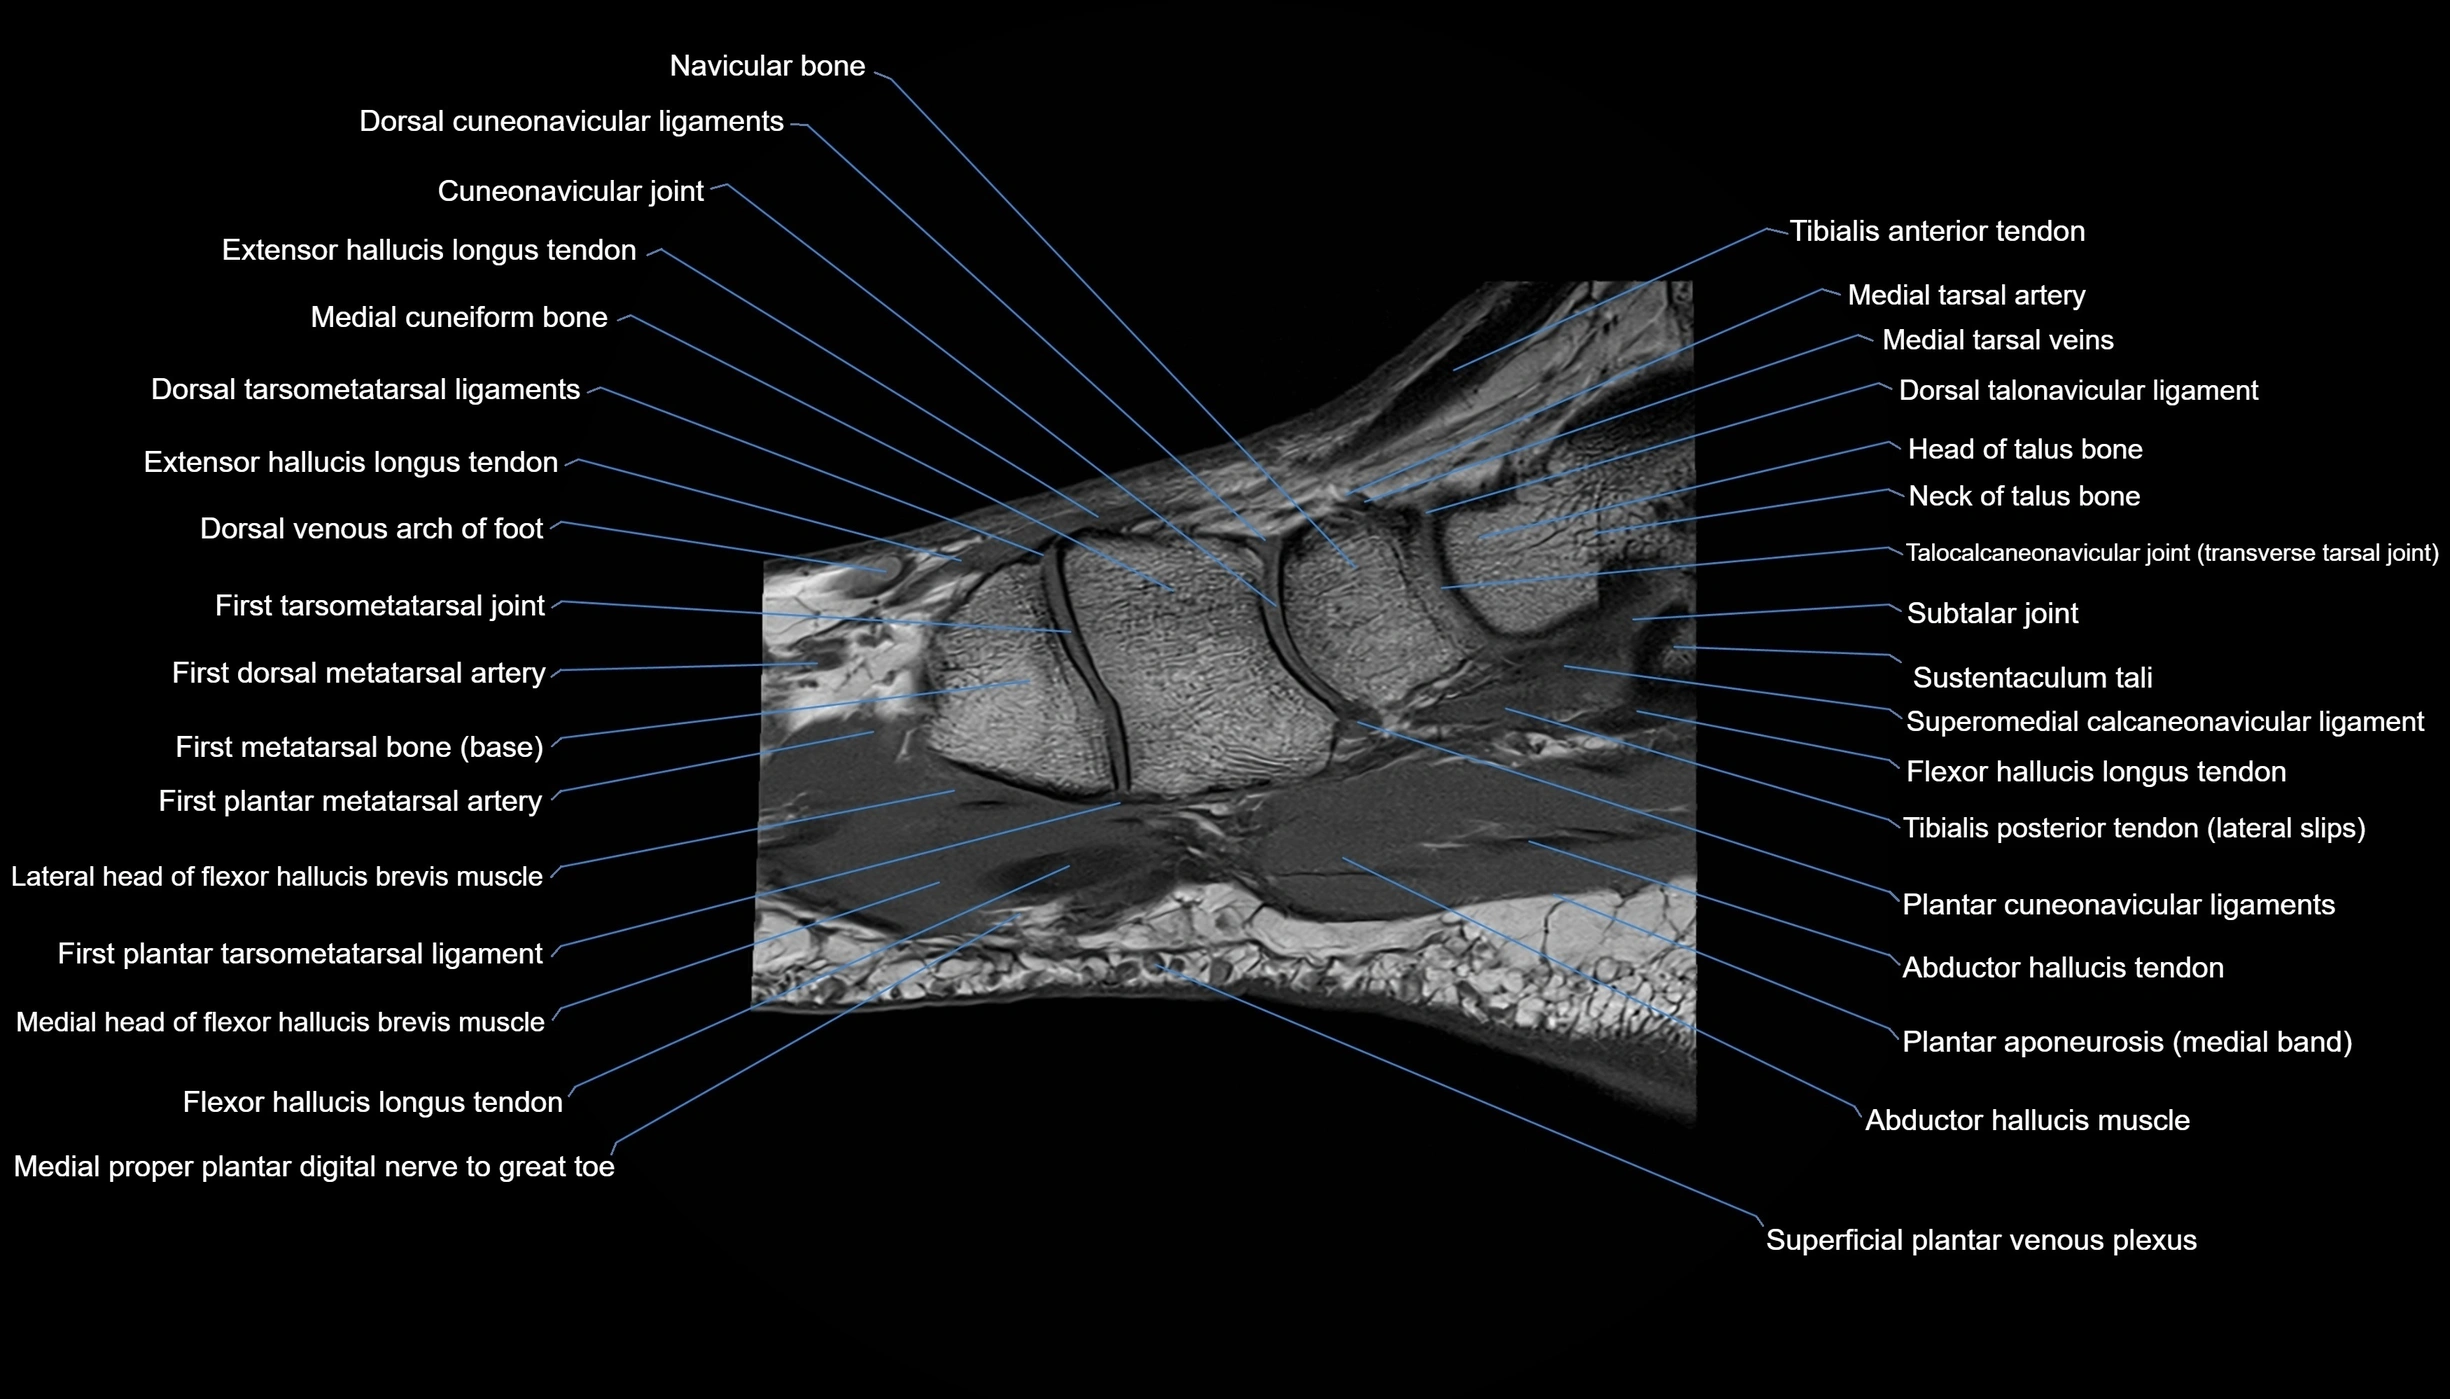

MRI image